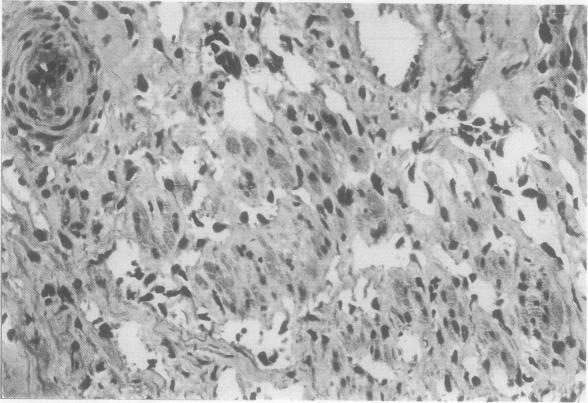

Pulmonary Kaposi's sarcoma may contribute to respiratory dysfunction in patients with acquired immune deficiency syndrome (AIDS) and features of pneumonitis. Opportunistic infections are readily recognised in endoscopic material, but pulmonary Kaposi's sarcoma is easily missed, so that patients are deprived of specific treatment. The clinical and pathological findings from nine cases of pulmonary Kaposi's sarcoma have been reviewed; these were found among 84 patients with AIDS and pneumonitis undergoing fibreoptic bronchoscopy and bronchoalveolar lavage. Diagnosis was established before death in eight patients (in five by bronchial biopsy and in three by open lung biopsy). Examination of lavage fluid showed alveolar haemorrhage in six patients. It is concluded that: (1) fibreoptic bronchoscopy may be useful in the diagnosis of endobronchial lesions of Kaposi's sarcoma; (2) alveolar haemorrhage in patients with AIDS is suggestive of pulmonary Kaposi's sarcoma. Factors that may cause difficulties in diagnosis include the focal nature of some lesions and the pleural or parenchymatous location of others. In addition, in the lung as in the skin, the early stages of Kaposi's sarcoma resemble granulation tissue. Such lesions are far more difficult to recognise than is the late nodular stage.

肺卡波西肉瘤可能导致获得性免疫缺陷综合征(AIDS)患者出现呼吸功能障碍及肺炎特征。在内镜检查材料中,机会性感染很容易被识别,但肺卡波西肉瘤很容易被漏诊,从而使患者得不到特异性治疗。回顾了9例肺卡波西肉瘤的临床和病理表现;这些病例来自84例接受纤维支气管镜检查和支气管肺泡灌洗的AIDS合并肺炎患者。8例患者在死亡前确诊(5例通过支气管活检,3例通过开胸肺活检)。对灌洗液的检查显示6例患者有肺泡出血。得出以下结论:(1)纤维支气管镜检查可能有助于诊断卡波西肉瘤的支气管内病变;(2)AIDS患者的肺泡出血提示肺卡波西肉瘤。可能导致诊断困难的因素包括一些病变的局灶性以及其他病变位于胸膜或实质内。此外,与皮肤一样,肺内卡波西肉瘤的早期阶段类似肉芽组织。这类病变比晚期结节阶段更难识别。